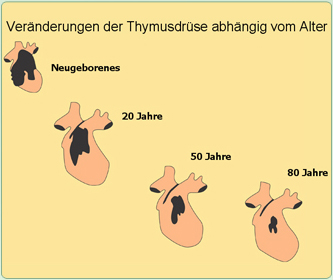

Mit zunehmendem Alter schrumpft die Thymusdrüse und damit nimmt die von den

Thymushormonen ausgehende Abwehr kontinuierlich ab.

Mit 50 Jahren sind nur noch 15 % des ehemaligen funktionsfähigen Thymusdrüsengewebes

vorhanden.

Das hat schwerwiegende Folgen: Die mit dem Alter zunehmende thymusbedingte

Abwehrschwäche durch Abnahme der wichtigen Thymuspeptide führt zu steigenden Infektionen, chronischen Krankheiten und Krebs.